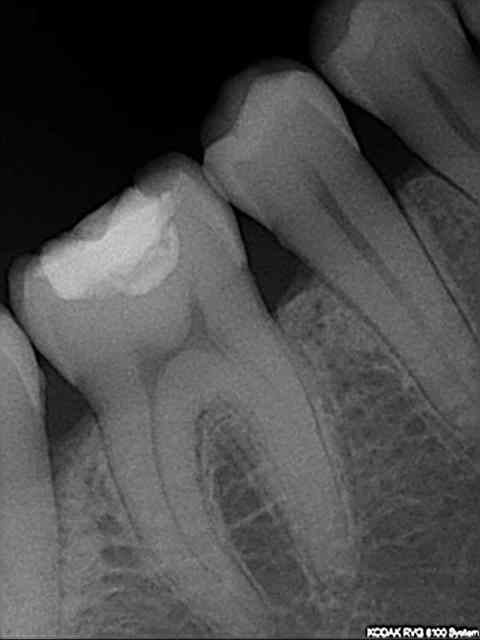

Patiente présente des douleurs au niveau de 46, provoquées principalement par la mastication.

46 présente un ancien composite légèrement infiltré.

Vitalité positive ; sondage normal ;

radio